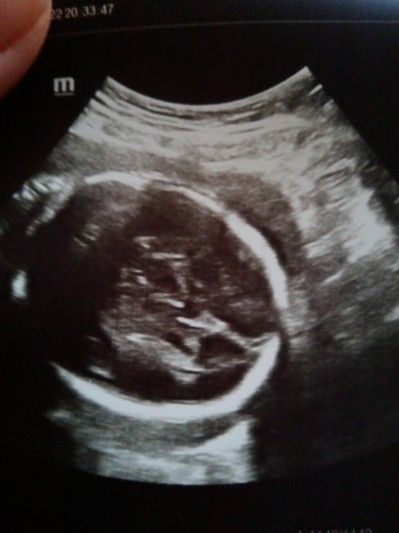

26+1 hamileyim doktor bu zamana kadar kız dedi 2 gün önce gittim erkeğe benziyor diyor böyle saçmalık olur mu bebek 26 haftalık olms ben hazırlık yaptım başına gelen var mı

Gebelik haftası 26+1

Hanımefendi burası çocuğun kafası resim ne alaka çözemedim ama . Bir iki hafta daha bekleyip başka bir doktora gorunun. Doktorunuz tam net görememiş demekki . Doğuma kadar cinsiyeti bilmeyen var cidden zor durum ya.  Minik kuşta gostermiyor tam demekki :))) kıyamam sağlıkla gelsin insallah

(150 puan)

Aslında gösteriyorda her gitmeme soruyoruz kız diyo bu sefer adamın erkek diyesi tuttu iki bacağının arasında minicik bı şişlik var ondan bahsediyo resmin sağ tarafı